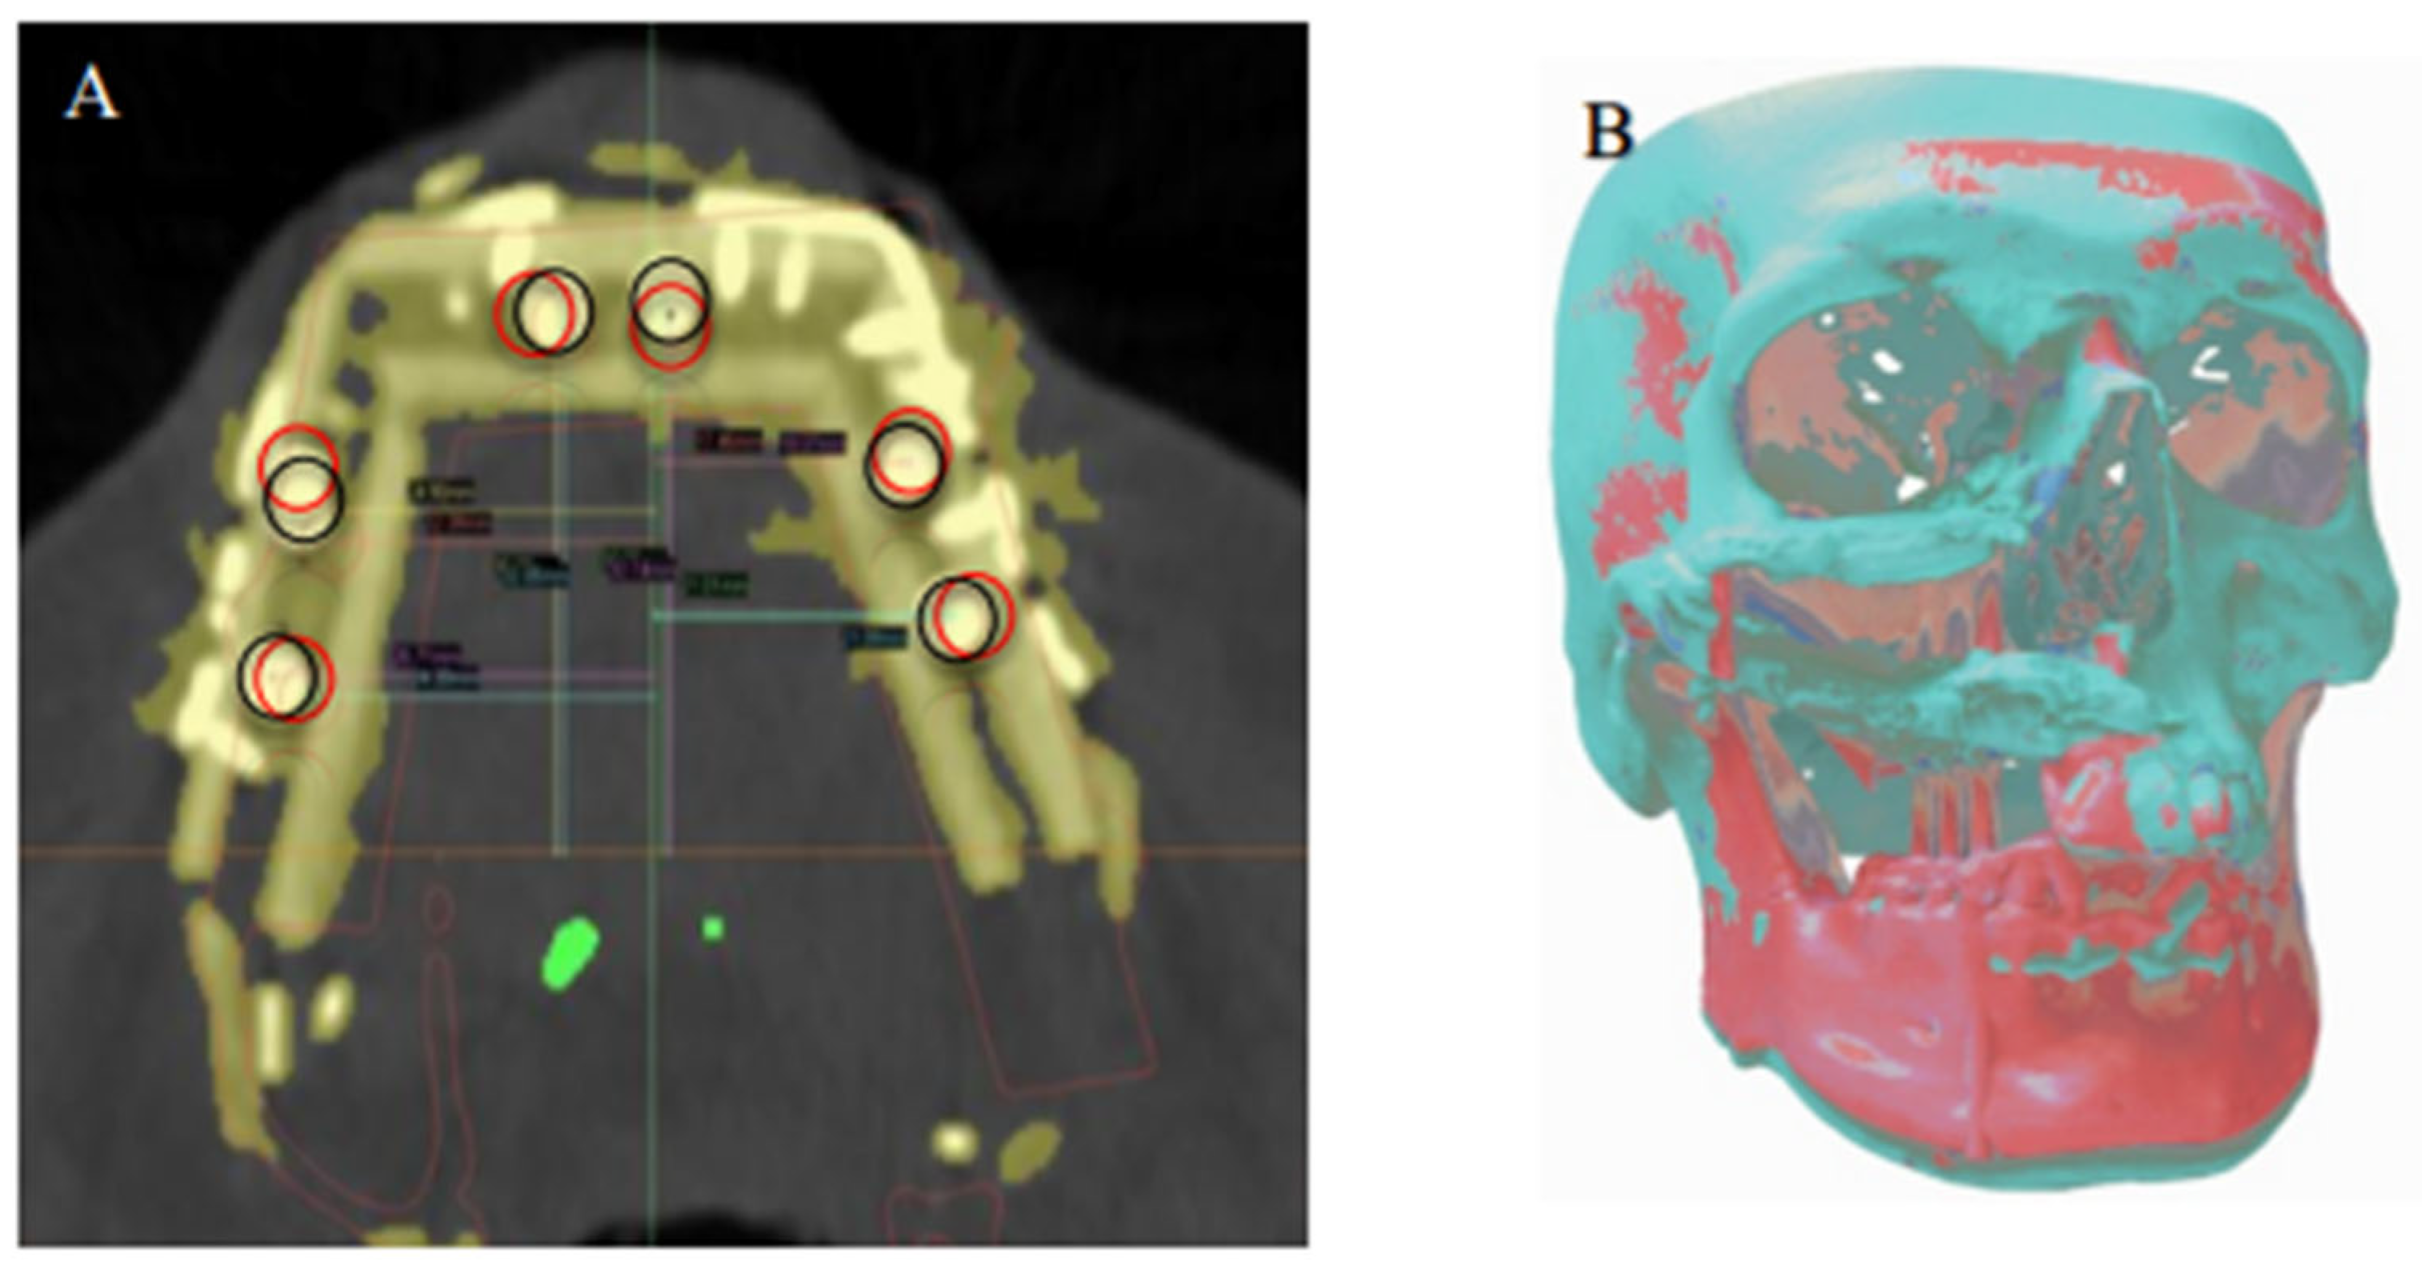

2.3. Virtual Surgical Planning

2.5. Primary Outcome

2.6. Data Analysis